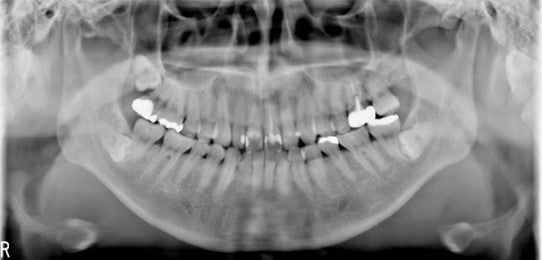

【図3‐1】の画像はCBCT/パノラマ複合機のフラットパネルで撮影されたパノラマ画像です。

全体的に画像にザラツキがありますが、特に真ん中の部分が白くなっています。これは、どうしても歯を全体的に撮影しようとすると頸椎が映りこんでしまう影響です。

見て頂けると分かるように、これでは特に前歯の部分の画像がボケて詳細な診断までは難しく、多くの歯科医が画像に対する不満をお持ちです。

従来製品の概念を打ち破り、CdTe半導体センサーで撮影した膨大なボリュームデータから画像ノイズを除いて見たい部分だけ出力することができるので、【図3‐2】の画像のように頸椎の影響がなく、骨梁構造が明瞭に描出された鮮明な画像出力ができます。